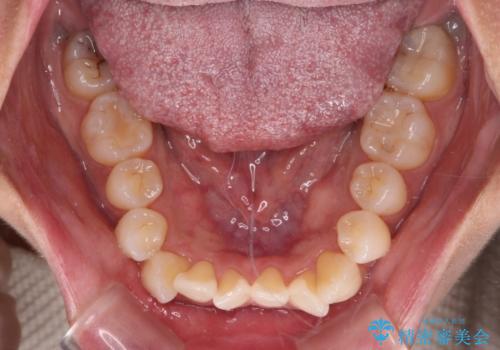

前歯のクロスバイト インビザラインによる矯正治療

- 上下のクロスバイトと前歯のデコボコを気にして来院された患者様です。

インビザラインを用い、IPR(歯と歯の間を削る)と歯列全体を拡大させることで、歯並びを整えていくこととしました。